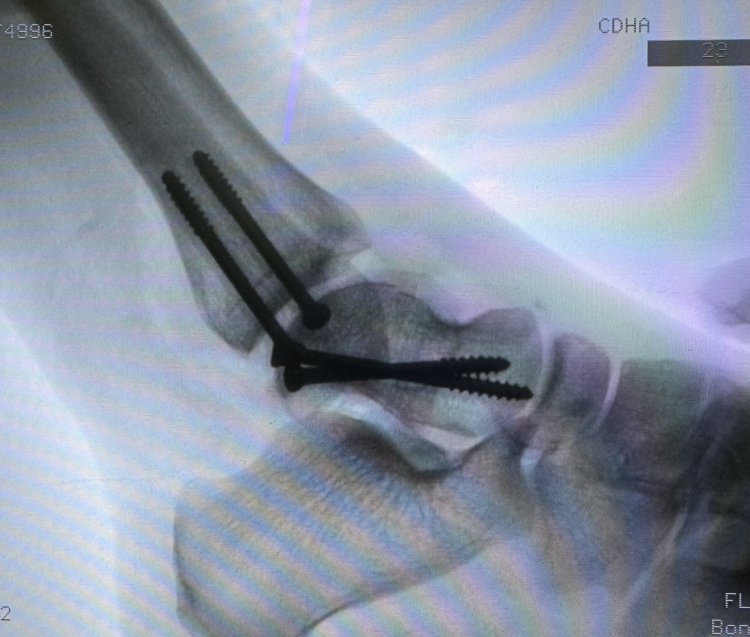

Vừa qua, Bệnh viện Hữu Nghị Việt Nam Cu - Ba Đồng Hới đã tiếp nhận và phẫu thuật bệnh nhân T.T.M.N 20 tuổi mang thai tuần thứ 40 bị tai nạn giao thông dẫn đến vỡ ối và vỡ phức tạp xương sên - một tổn thương rất khó gặp và rất ít được thấy trong chấn thương.

Trước đó, bệnh nhân được chuyển đến khoa Cấp cứu trong tình trạng đa chấn thương, đa xây xước và vỡ ối vì tai nạn giao thông, chẩn đoán gãy xương sên cổ chân trái. Rất nhanh chóng, các bác sĩ đã đặt cố định bột, làm các xét nghiệm cận lâm sàng và liên hệ hội chẩn Sản khoa để có phương án điều trị tốt nhất cho bệnh nhân và thai nhi.

“ Ca phẫu thuật được ekip khoa Ngoại chấn thương chỉnh hình và khoa Gây mê hồi sức hoàn thành tốt đẹp với kĩ thuật mổ sử dụng Osteotomy Chevron cùng đường mổ trước trong kinh điển nhằm có thể quan sát và đưa mặt khớp về đúng vị trí” - TS.BSNT Nguyễn Phạm Tuấn, khoa Ngoại CTCH - Phẫu thuật viên chính của kíp mổ cho biết.